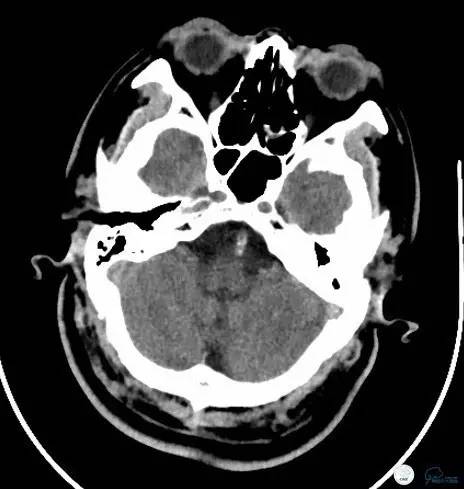

术后给于抗血小板、抗凝、降脂等规范药物治疗。术后24小时复查头颅CT(图14-15):未见出血。

图14

图15